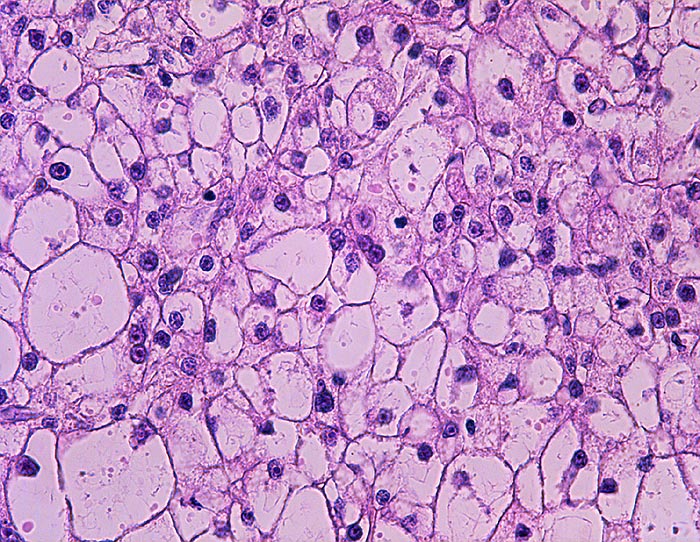

PathoPic – image database / PathoPic ID 1229 - Hepatozelluläres Karzinom klarzellig : Ovarmetastase

Hepatozelluläres Karzinom klarzellig : Ovarmetastase

Bienenwabenartig angeordnete Tumorzellen mit reichlich klarem Zytoplasma.

St.n. Lebertransplantation wegen Hepatozellulärem Karzinom bei Zirrhose und chronischer Hepatitis C vor 2 Jahren. Jetzt Metastasen von 12 und 14cm Durchmesser in beiden Ovarien.